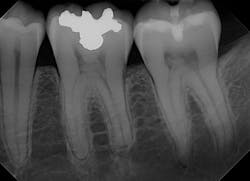

DentiMax LLC's Dream Sensor digital sensor system

Unless you are using a CAD/CAM milling unit, the most expensive item in your office that gets used every day is probably your digital radiographic sensor. We pay thousands and thousands of dollars for these pieces of plastic that plug into our computers. We use them multiple times a day, beat the hell out of them, and expect them to work every time without exception. We ask a lot of our digital radiographic sensors. I think it's OK to ask yourself periodically if you have the right ones for your practice.

A couple of big-name companies are top of mind when it comes to digital radiography sensors, just like with other types of dental products. Oftentimes, we see smaller companies come to market with advances and improvements that the big companies can't achieve. The DentiMax Dream Sensor is a perfect example of that.

For a digital radiographic sensor, the Dream Sensor is a workhorse. The Dream Sensor has three qualities that make it worth comparing to the big names on the market. First, the images are crystal clear because of the CMOS active-pixel technology inside the sensor. The circuitry and engineering are state of the art.

Second, comfort is a huge advantage. The DentiMax Dream Sensor is the thinnest CMOS sensor available. Thinner, rounded edges provide an easier, more comfortable experience for your patients. We can all agree about how important that is. In fact, many pediatric offices use the Size 1 Dream Sensor for kids, who are notoriously tough to use sensors on.

The third big advantage of the DentiMax Dream Sensor is its hardware and software compatibility. As an open system, the Dream Sensor works well with most major software systems. Many other digital sensor systems use proprietary file types that make importing and exporting difficult-but not DentiMax!

DentiMax offers imaging software that works well with other systems, as well as practice management software, which is unique. All of this-the sensors and software-is significantly less expensive than similar products from big-name competitors. DentiMax gives dentists options for thinking outside the box when it comes to the hardware and software needed for practicing in the 21st century! Line-drive single up the middle for DentiMax!